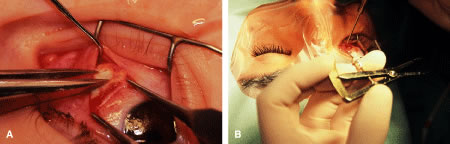

A no. 15 surgical knife or other similar instrument is used to penetrate the conjunctiva at the limbus (Fig. 50). Care is taken to approach the limbustangential to the globe so that inadvertent penetration of the sclera or cornea is avoided. A Westcott scissors also may be used to incise the conjunctiva at the limbus. To facilitate this step, conjunctiva is lifted gently with a 0.5-mm Castroviejo forceps (see Fig. 50).

|

A single-armed 6-0 synthetic absorbable suture is passed through the muscle tendon near its insertion (Fig. 57). A double-lock bite is taken with the needle, and the suture is tied with two square knots to secure it to the upper and lower poles of the tendon of the rectus muscle. The muscle is lifted or tented off of the surface of the globe with a Jameson hook. A Westcott scissors is used to cut the muscle free (Fig. 58).

Incision is made into the conjunctiva at the limbus (Fig. 64).

|